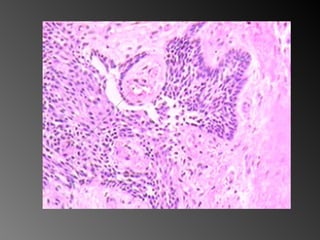

Lâmina 2 Fonte Allan Giovanini

Lâmina 2 FonteAllan Giovanini